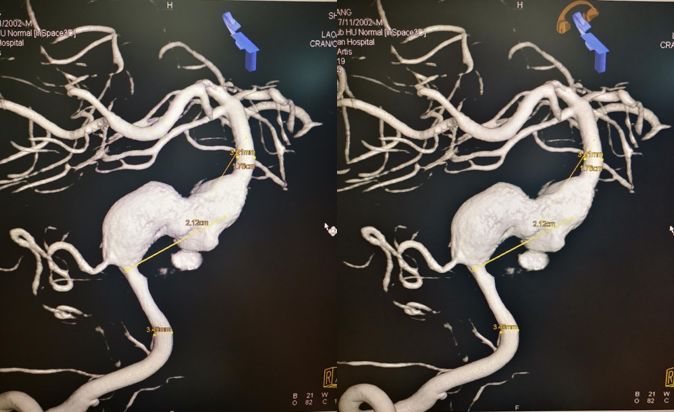

术前右椎动脉3D造影

术前左椎动脉造影显示:基底动脉中下段夹层动脉瘤,左侧小脑后下动脉夹层动脉瘤。

经过手术讨论,由于患者病情复杂,且目前症状主要是基底动脉夹层动脉瘤所致,拟一期经右侧椎动脉行基底动脉夹层动脉瘤PED支架植入术。而二期行左侧小脑后下动脉PED支架植入术及颈动脉夹层动脉瘤支架植入术。

根据椎动脉3D造影测量结果,拟选择3.75 mm*35 mm的PED支架。